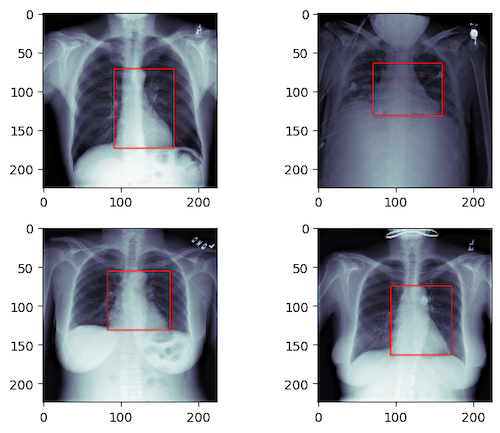

The goal for this part is to predict a bounding box containg heart in the above X-Ray images.

The task can be formulated as a regression problem. Again the input is the image but the output is a 4d vector (xmin, ymin, xmax, ymax) which defines the location of the heart as illustrated below. Here the Mean Square Error is used as the loss function.

After training for 100 epochs, the MSE for the algorithm is ~40 indication the predicted bounding box are about 3 ~ 5 pixel off the ground truth.